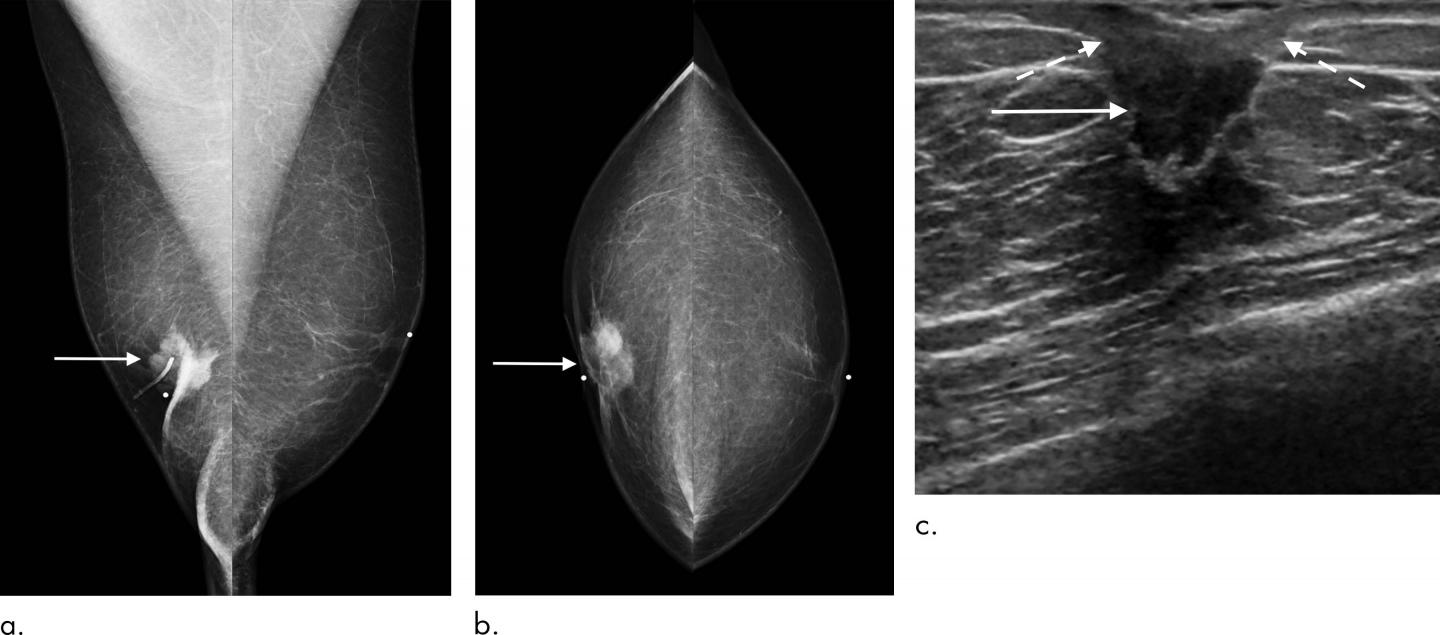

OAK BROOK, Ill. - Selective mammography screening can provide potentially lifesaving early detection of breast cancer in men who are at high risk for the disease, according to a landmark study published in the journal Radiology .

In the first study of its kind, Dr. Gao and colleagues evaluated breast imaging utilization patterns and screening outcomes in 1,869 men, median age 55, who underwent mammography over a 12-year period.

Mammography helped detect a total of 2,304 breast lesions, 149 of which were biopsied. Of those, 41 (27.5 percent) proved to be malignant. The cancer detection rate of 18 per 1,000 exams in men at high risk of breast cancer was significantly higher than the average detection rate of three to five per 1,000 exams in average risk women. In addition, the cancers in men detected were at an early stage, before they had spread to the lymph nodes, improving the prognosis for survival.

In men, mammographic screening sensitivity, or the ability to detect cancer, was 100 percent, while specificity, or the ability to distinguish breast cancer from other findings, was 95 percent. This excellent performance is related to men having a relative lack of breast fibroglandular tissue that in women often masks abnormal results, the researchers said.